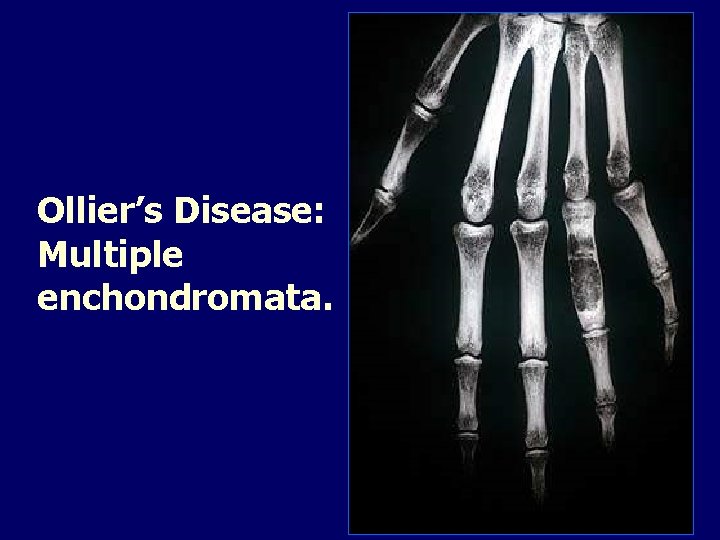

Ollier’s Disease: Multiple enchondromata.